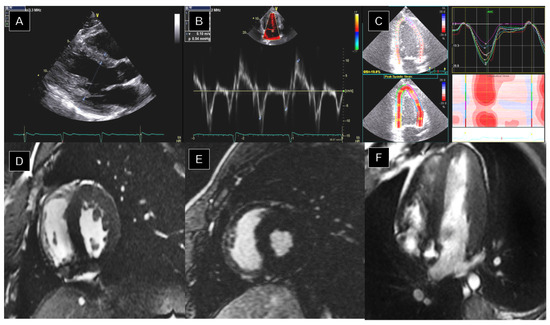

5.1. Dilated Cardiomyopathy (DCM)

5.2. Hypertrophic Cardiomyopathy (HCM)

5.3. Arrhythmogenic Cardiomyopathy (ACM)

5.4. Left Ventricular Non-Compaction (LVNC)